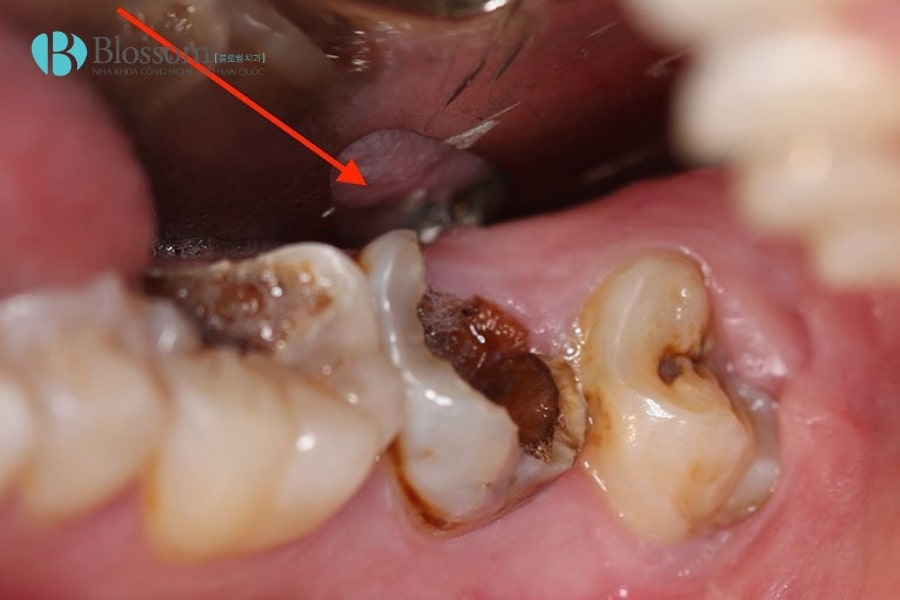

Việc tự ý “làm chết tủy” răng tại nhà bằng mẹo dân gian hay nguyên liệu tự nhiên không những không có tác dụng điều trị, mà còn tiềm ẩn nhiều biến chứng nguy hiểm. Tủy răng là bộ phận sống, chứa mạch máu và dây thần kinh, nên mọi can thiệp sai cách đều có thể dẫn đến nhiễm trùng, đau nhức nặng và mất răng. Dưới đây là những nguy cơ thường gặp:

- Nhiễm trùng và viêm nặng hơn: Các mẹo dân gian không thể loại bỏ mô tủy viêm, khiến vi khuẩn tiếp tục phát triển và lan rộng.

- Nguy cơ áp xe xương hàm: Vi khuẩn từ tủy viêm có thể đi xuống chóp răng, tạo ổ mủ (áp xe), gây sưng má, đau dữ dội.

- Nguy cơ nhiễm trùng máu: Nếu nhiễm trùng lan vào mạch máu, người bệnh có thể đối mặt với tình trạng nhiễm trùng huyết cực kỳ nguy hiểm.

- Lây lan sang các răng bên cạnh: Viêm tủy không được xử lý đúng cách có thể gây sâu và viêm lan sang các răng kế cận.

- Tiêu xương ổ răng và mất răng: Viêm kéo dài làm tiêu xương, khiến răng yếu, giòn, dễ gãy và buộc phải nhổ bỏ.

Những nguy cơ và biến chứng khi tự làm chết tủy răng tại nhà